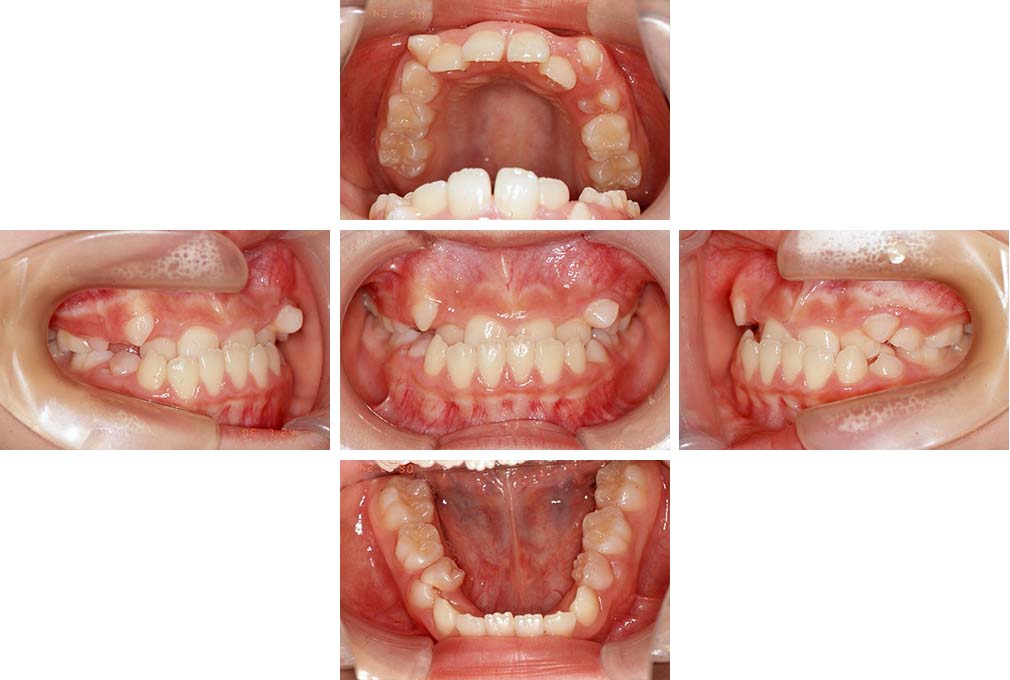

CASE:02

下顎前歯部叢生、小臼歯4歯先天欠損

初診時年齢 14歳3か月

性別 女性

治療費の目安 70万円(治療開始時)

上顎左右側小臼歯3歯、下顎左側第二小臼歯の先天欠損と下顎前歯の叢生を主訴として近隣一般歯科から紹介来院した。

上顎左側第一、第二小臼歯、右側第一小臼歯、下顎左側第二小臼歯が先天欠損であったが、左上第二乳臼歯の根の吸収がほぼ無いことから、これを残すこととして、下顎左側乳臼歯と、右側第二小臼歯を抜歯していただきマルチブラケット装置を使用して動的治療を行った。矯正用ゴムなどの協力状態も良く2年0カ月(調整来院19回)で装置を撤去し保定へ移行した。動的治療終了13年2カ月での来院時には下顎左右側智歯が萌出していたが、垂直的に萌出していたため抜歯は行っていない。

治療前

14歳3か月

治療後

動的治療期間2年0カ月

16歳7か月

13年経過

動的治療終了後13年2カ月

30歳0か月